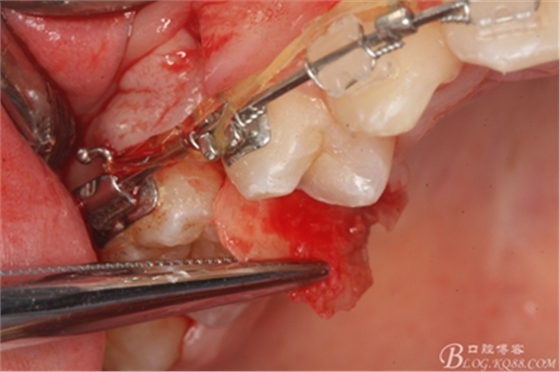

圖13. 用小球鉆去除約1mm牙槽骨,暴露15牙根面約5mm。

圖14.用小球鉆縱分15牙根

圖15 .微創(chuàng)挺把15牙根縱分成近遠中兩塊